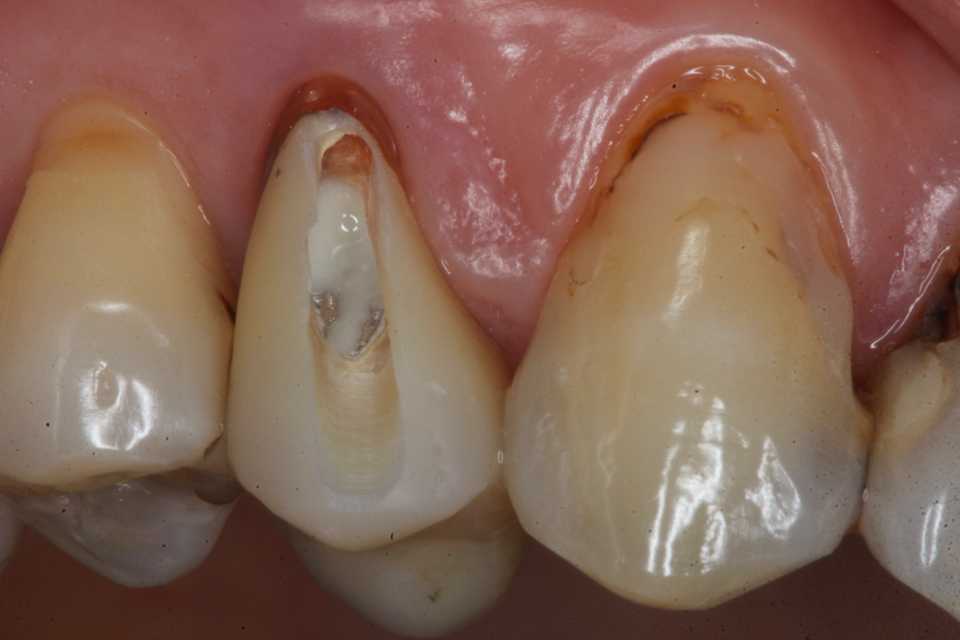

40代女性、右上4、Per+GAPerというのは根管治療後に根管内に感染を起こしている状態でGAとは炎症が根管の外に波及している状態。この方は10年程前に神経を取って被せたということでしたが、2、3年前GAができて別の歯医者に行ったら切って膿を出してもらったら治ったということでしたが、根管に細菌が感染している以上細菌が消えたりしないので、何度も再発します。今回は切開というよりは根管内部に3MIX+α-TCPを入れて根管内部を消毒殺菌しようというコンセプト。内部のポストも根管充填材も完全に除去する必要はない。根管充填材が見えるところまで穴を開けて薬剤を入れ、CRで蓋をするだけでよい。信じられないだろうが、これだけで治る。もし再発するようなら、冠のどこかに隙間があり、そこから細菌が出たり入ったりしているわけだから、冠もポストも除去して隙間を塞ぐ必要がある。多分従来の根幹治療しか知らない歯科医師は何が起こっているのか分からないと思うが、根管治療の真実が分かれば理解できないことはないと思う。一般に思われてる根管治療というのは理想からは程遠いものだということだ。冠にもポストにも根管充填材にも隙間だらけで細菌がその隙間から出入りしているのが現実だ。

僕が使っているボンディング材は​ こちら ​。α-TCPの50%クエン酸練り(硬化する)。

この上からCRダイレクトボンディングでカバーする。​ 3MIX+α-TCP

では時系列でどうぞ